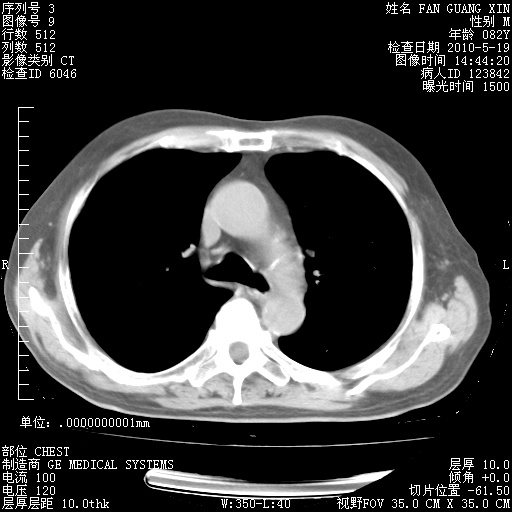

复查肺部CT,明显好转。为什么发热呢?

治疗3周后的肺部CT

治疗3周后的肺部CT纵隔窗